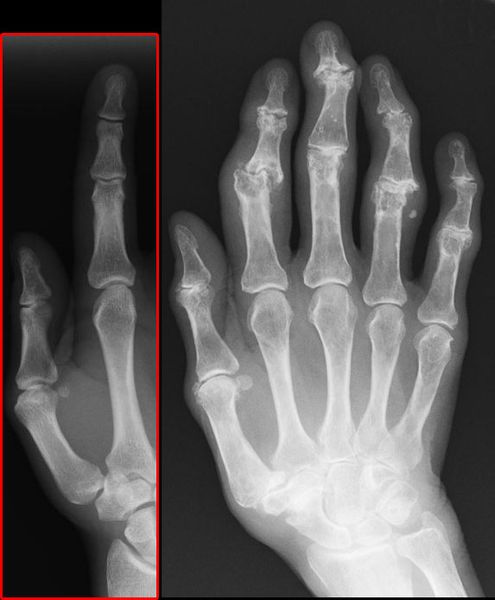

(Bild: J. Lengerke - Eigenes Werk, CC BY-SA 3.0, https://de.wikipedia.org/wiki/Arthrose#/media/File:Roe-heberden.jpg) (Bild: J. Lengerke)